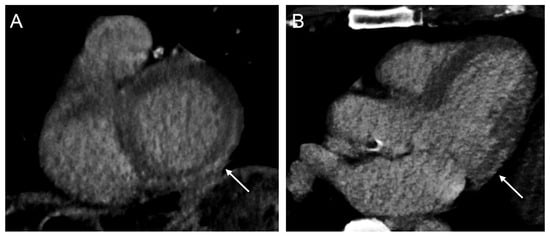

3.2.2. Scar Identification

- Behar, J.M.; Rajani, R.; Pourmorteza, A.; Preston, R.; Razeghi, O.; Niederer, S.; Adhya, S.; Claridge, S.; Jackson, T.; Sieniewicz, B.; et al. Comprehensive use of cardiac computed tomography to guide left ventricular lead placement in cardiac resynchronization therapy. Heart Rhythm 2017, 14, 1364–1372. [Google Scholar] [CrossRef]

- Pezel, T.; Mika, D.; Logeart, D.; Cohen-Solal, A.; Beauvais, F.; Henry, P.; Laissy, J.P.; Moubarak, G. Characterization of non-response to cardiac resynchronization therapy by post-procedural computed tomography. Pacing Clin. Electrophysiol. 2021, 44, 135–144. [Google Scholar] [CrossRef]

- Fyenbo, D.B.; Sommer, A.; Kühl, J.T.; Kofoed, K.F.; Nørgaard, B.L.; Kronborg, M.B.; Bouchelouche, K.; Nielsen, J.C. Transmural Myocardial Scar Assessed by Cardiac Computed Tomography: Predictor of Echocardiographic Versus Clinical Response to Cardiac Resynchronization Therapy? J. Comput. Assist. Tomogr. 2019, 43, 312–316. [Google Scholar] [CrossRef]